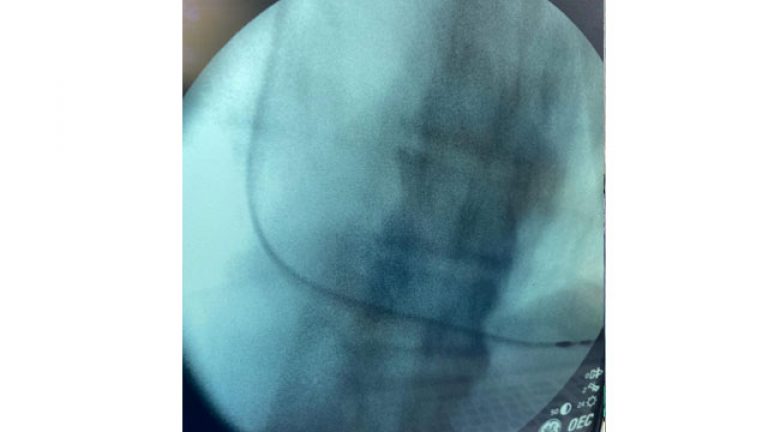

Las bradiarrítmias se controlan muy bien con marcapasos, de tipo auricular o de ambas cámaras, mientras que las taquiarritmias responden al tratamiento médico. Sin embargo, debido a que ambos cuadros pueden presentarse al mismo tiempo, los fármacos que controlan las taquiarritmias pueden empeorar las bradiarritmias. Por lo tanto, se implanta un marcapasos antes de comenzar la terapia medicamentosa para cualquier taquiarritmia, en caso de que las dos patologías aparezcan simultáneamente.

La colocación de marcapasos en pacientes con síndrome del seno enfermo reduce la incidencia de fibrilación auricular, eventos tromboembólicos, insuficiencia cardíaca y la tasa bruta de mortalidad.[1] En ocasiones se indica un procedimiento con catéter, llamado ablación por radiofrecuencia, para eliminar las taquicardias.[2] No está indicado el tratamiento en pacientes asintomáticos.[3]